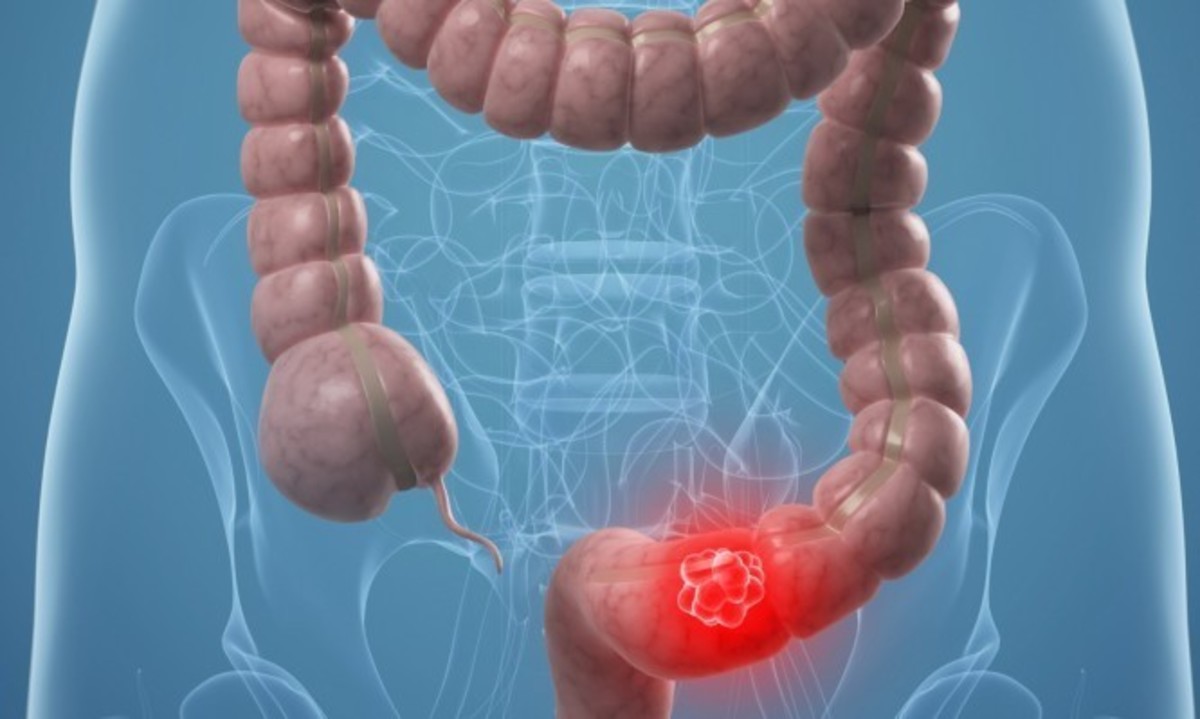

Καρκίνος: Βίντεο που συγκινούν και ενημερώνουν από την Εταιρεία Ογκολόγων Παθολόγων Ελλάδος

Με δυνατό μήνυμα "Ο καρκίνος δεν είναι πια ανίκητος" και παροτρύνοντας όλους του πολίτες να "ενημερωθούν και να μην φοβούνται" η ΕΟΠΕ δίνει το στίγμα για την αυριανή Παγκόσμια Ημέρα κατά του Καρκίνου.